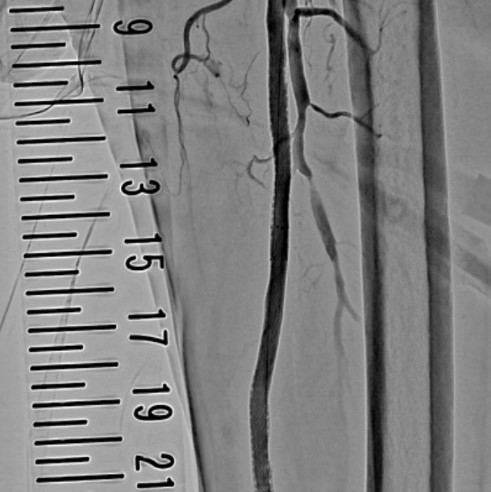

四肢血管撮影

四肢の血管造影では、腕や足などの動脈硬化などで狭くなった血管に対してカテーテルを挿入し風船やステント等で狭窄部位を拡張し、抹消への血流を改善する治療を行います。

左下肢動脈造影

左浅大腿動脈閉塞

術後動脈造影